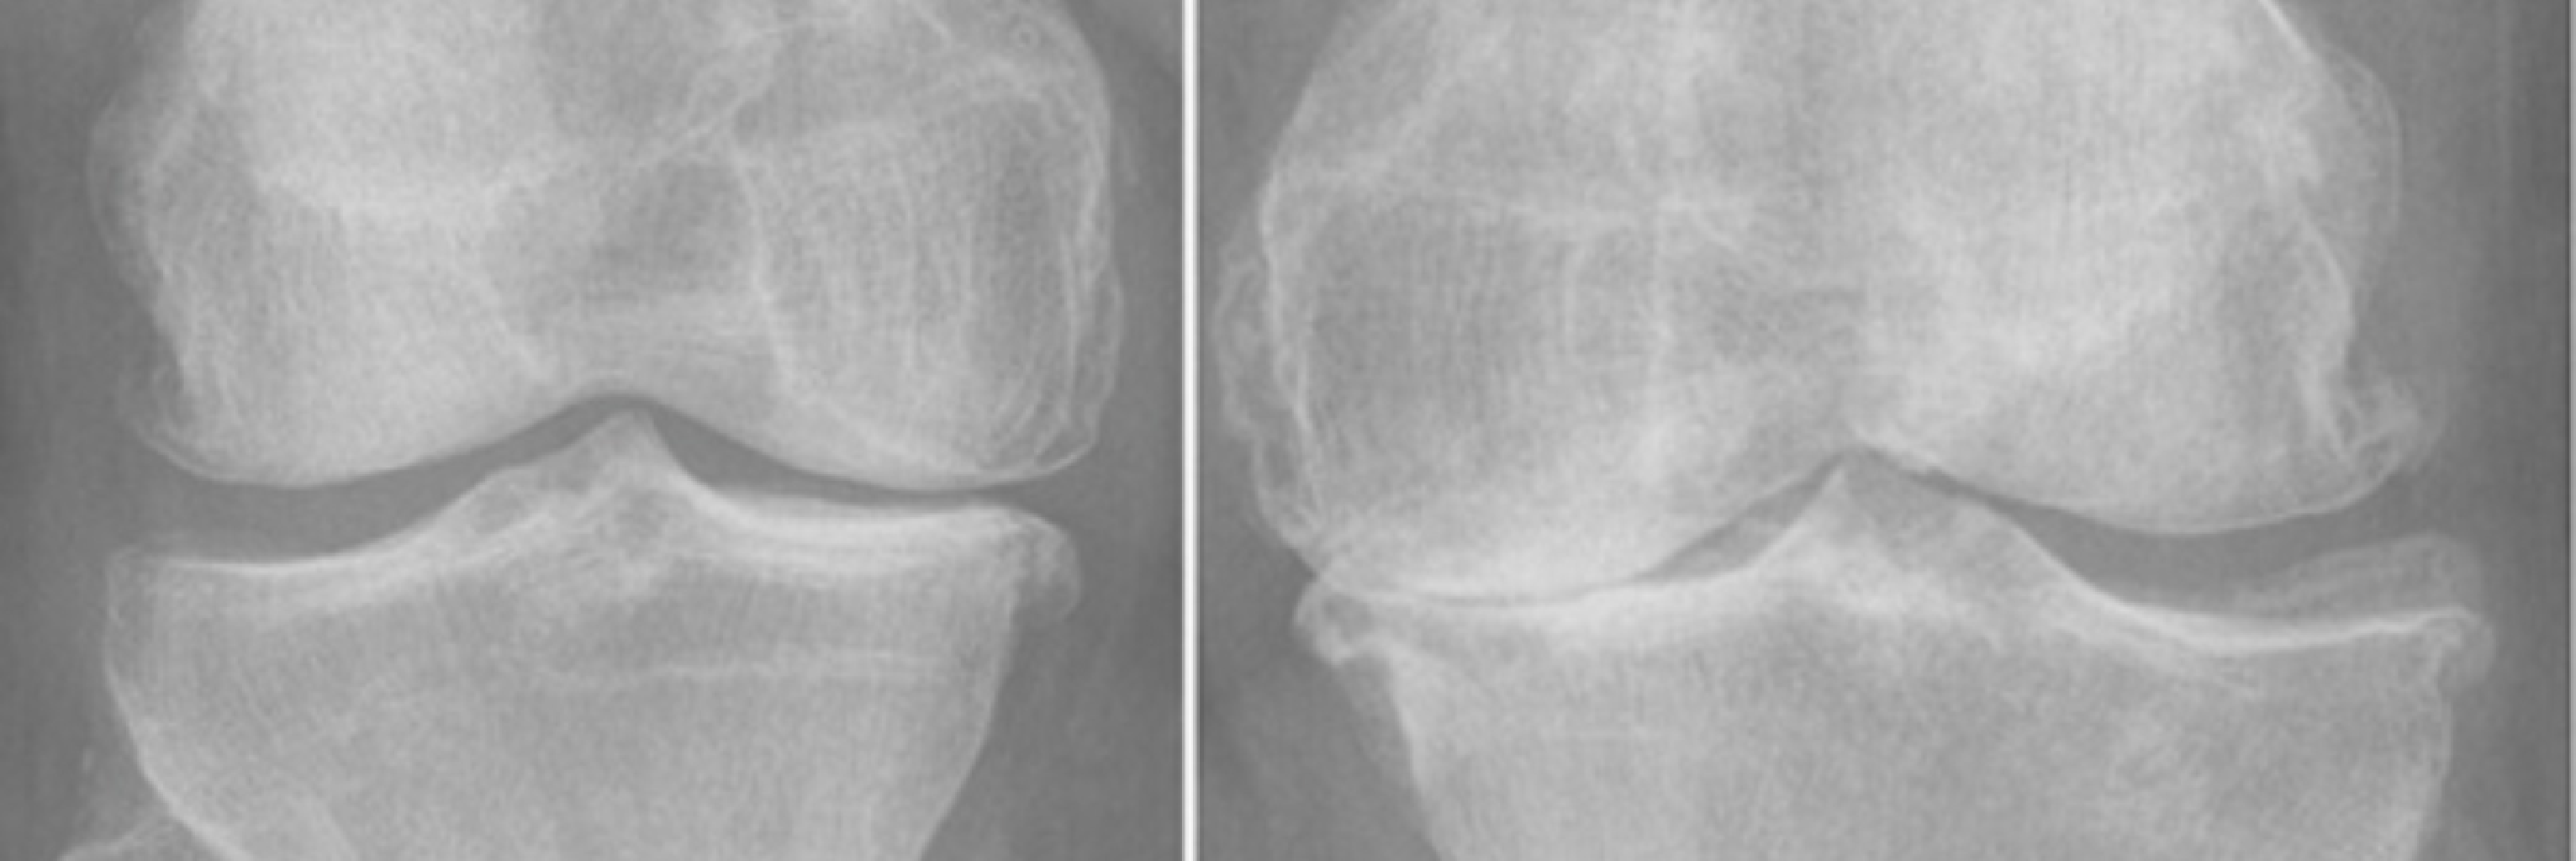

Diz Protezi Ameliyatı: Hastalar İçin Kapsamlı Bilgilendirme Giriş Diz eklemi, günlük yaşamda e...